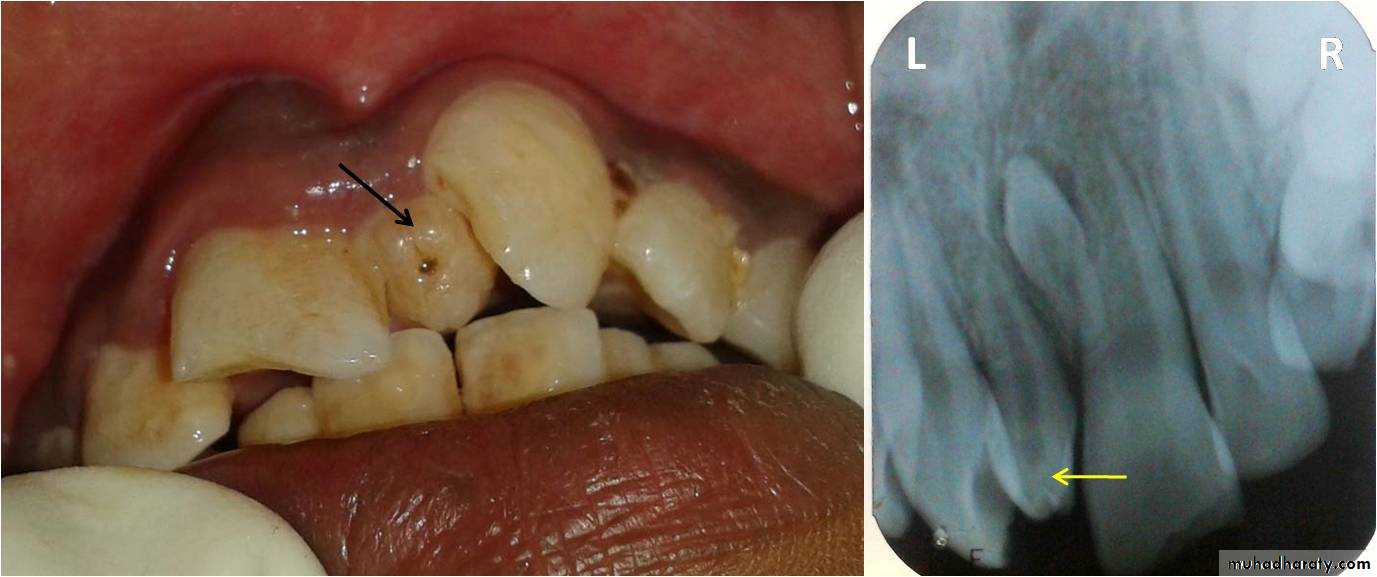

Dilacerated incisors :

Trauma to the deciduous incisors especially in the 2-3 years of age can cause damage to the underlying permanent incisor tooth germ causing root development to take place at an angle.Exposure and orthodontic traction can be performed if possible, but if not, these teeth should be removed and the lateral incisors allowed filling their space.

It is essential to seek the opinion of an orthodontist.